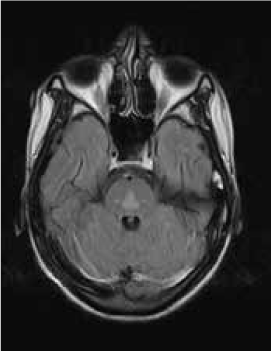

Magnetic resonance imaging (MRI) of the brain showed symmetrically increased T2-weighted and fluid-attenuated inversion recovery signal in the central pons (Figure 1) and in the striatum of the basal ganglia (Figure 2), with no contrast enhancement seen on corresponding T1-weighted postgadolinium images (Figures 3 and 4). Spinal MRI (Figure 5) demonstrated high signal on T2-weighted images from the area postrema in the medulla extending caudally to the T9 thoracic segment, with marked cord swelling and mild enhancement on T1-weighted postcontrast studies (Figure 6), in keeping with a longitudinally extensive inflammatory myelitis.

Magnetic resonance image of brain shows symmetrical, central high signal in pons on axial fluid-attenuated inversion recovery sequences

The clinical and radiologic features supported the diagnosis of NMO. However, the symmetrical pontine and basal ganglia high signal without contrast enhancement were considered to be strongly suggestive of concomitant ODS (pontine and extrapontine myelinolysis).

Neuromyelitis optica may lead to hyponatremia via at least two mechanisms. Area postrema involvement frequently causes intractable vomiting, and this may result in a low serum sodium level. Moreover, the syndrome of inappropriate antidiuretic hormone may develop in patients with NMO and hypothalamic lesions. In the present patient, the lowest recorded sodium level was 132 mmol/L. However, MRI demonstrated features of both central pontine and extrapontine myelinolysis, which, when occurring together, are considered virtually pathognomonic of ODS.4 Typical features include the symmetrical nature of the changes, the involvement of areas typically affected in ODS (pons, basal ganglia), and the sparing of peripheral pontine fibers. However, it remains a possibility that these radiologic changes were due to NMO primarily rather than osmotic demyelination. In a recent review, Kim et al.5 expanded on the range of MRI abnormalities consistent with NMO and NMO spectrum disorders. Gray matter demyelination of the thalamus and bilateral involvement of the corticospinal tracts have been described, although published examples are not as strikingly symmetrical as in this case and do not show the combination of central pontine demyelination with symmetrical striatal involvement.5 To our knowledge, these typical ODS changes in the context of NMO have been described in only one other case, in the Japanese literature.6